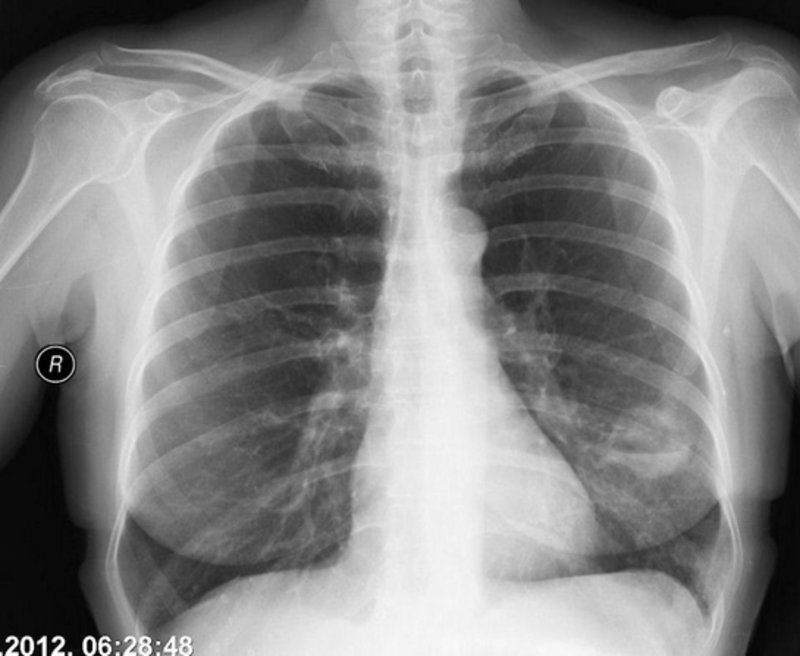

Akciger Rontgeni Hayat Kurtarici Olabilir